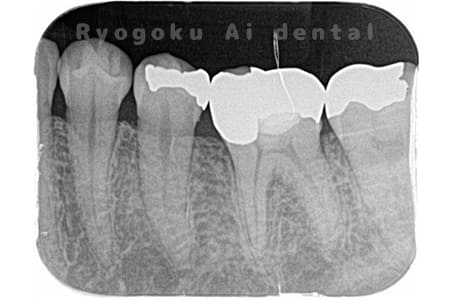

Case04

-

- 原因

- 右下6番パーフォレーション

- 治療内容

- パーフォレーションリペア

- 治療費用

- ¥66,000

右下奥歯が他院で行った治療後、腫れが引かないとのことでご来院された患者様です。近心根の遠心壁にパーフォレーションを認めたため、外科的にパーフォレーション部の修復を行いました。経過良好です。

<リスク・副作用>

手術後は痛み、腫れ、痺れ、青あざなどの副作用が生じます。痛みは痛み止めを処方しますが、腫れ、青あざは1週間程度生じる場合があります。また、部位によっては神経の走行が複雑で、痺れが残り、長期的にお薬を処方する場合があります。